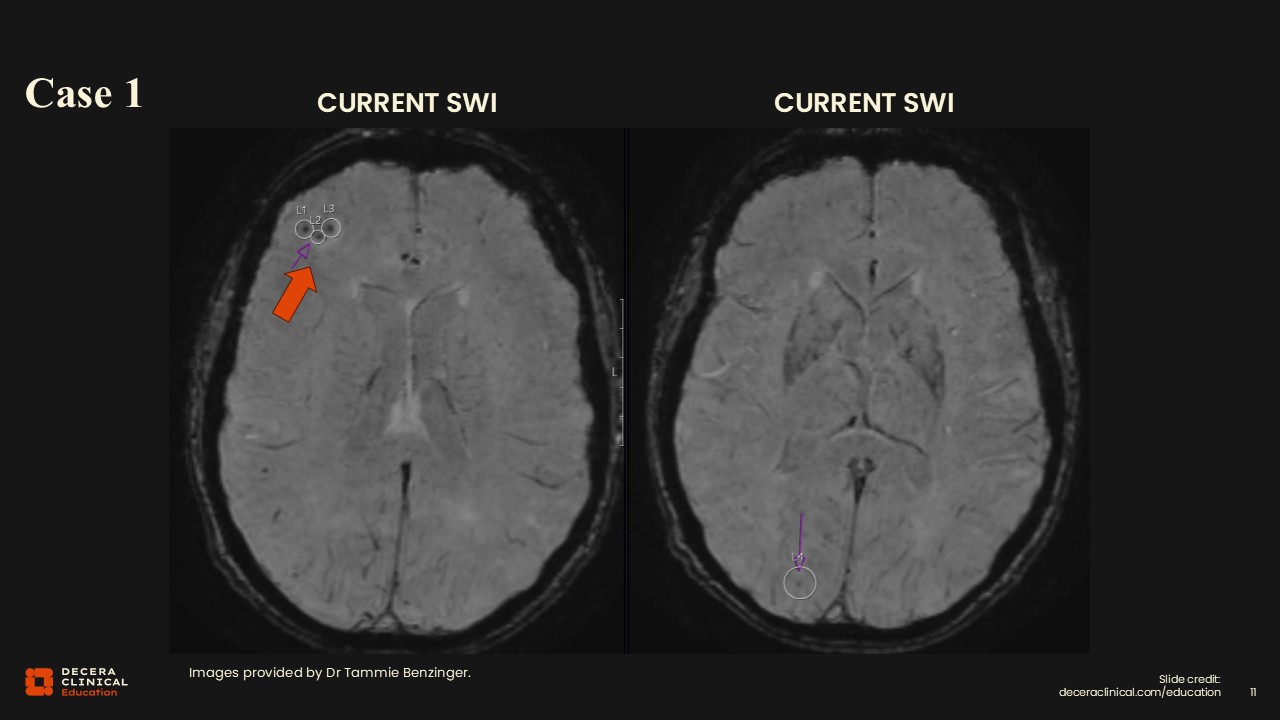

Case 1: Detection of ARIA-H

SWI in the same regions as the ARIA-E demonstrated 3 microhemorrhages in the right frontal lobe and 1 microhemorrhage in the right occipital lobe, consistent with ARIA-H. As is often the case, ARIA-H lesions appeared in the same locations as ARIA-E, although in some patients either the edema or the hemorrhagic component may be easier to recognize.